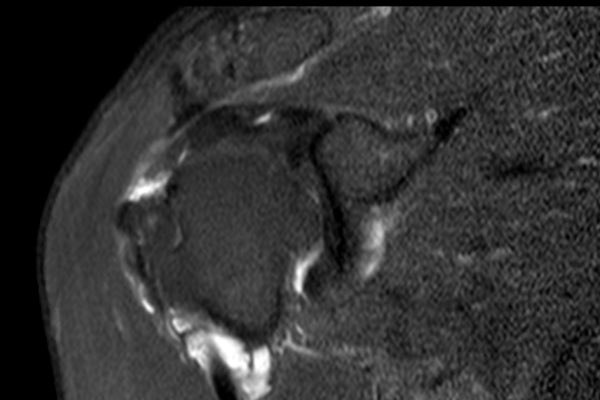

Nhấp vào hình ảnh để phóng to, sau đó cuộn qua các lát cắt.

Có hình ảnh rách toàn bộ chiều dày gân cơ trên gai kèm co rút và teo cơ.

Lưu ý các dải mỡ trong cơ tròn bé, cơ trên gai và cơ dưới gai.